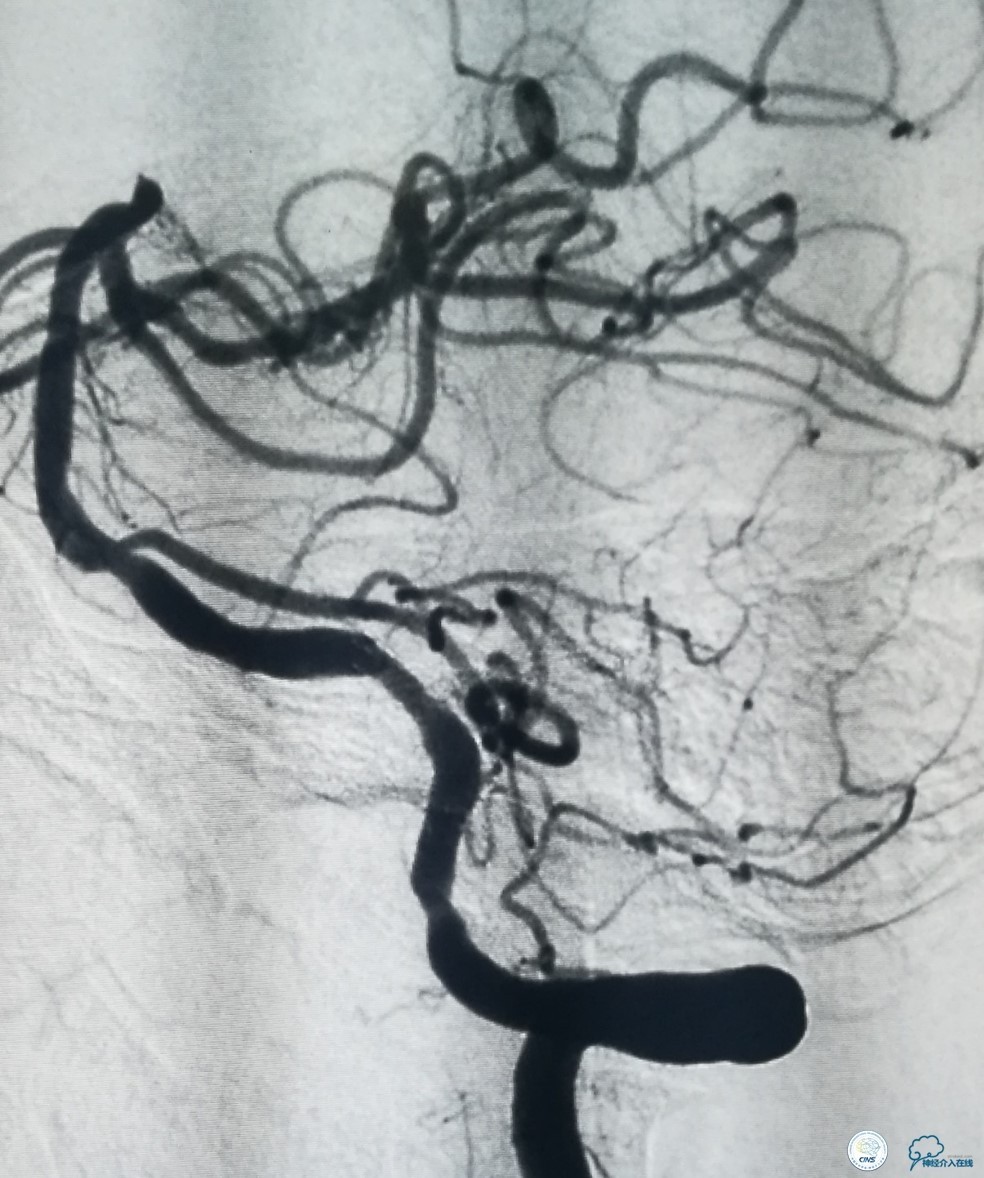

其后放置Wingspan支架(3.5 mm× 15mm),释放后造影见支架贴壁良好,远端血管显影好,前向血流TICI3级(图10)。

图10